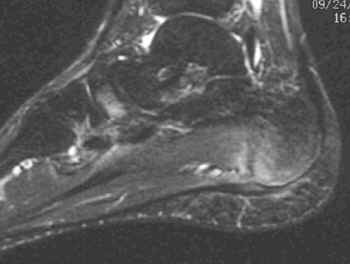

Partial thickness rupture of plantar fascia

MR imaging shows localized thickening of plantar fascia with abnormal intrafascial intermediate to high signal intensity on T1W and T2W images. Interuption of some fibers of plantar fascia and edema of the surrounding soft tissues can also be seen.